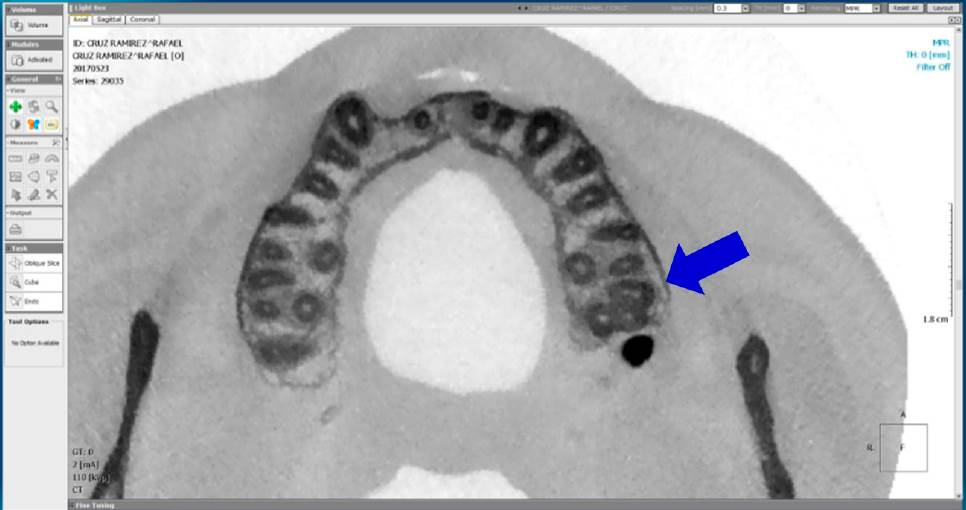

Se realizó el análisis de CBCT a cada diente para confirmar la presencia o ausencia del conducto MV2. Se usó la misma computadora con lector de CD y el programa OnDemand3DTM (Cybermed Inc., Daejeon, Korea). Se consideró presente el conducto, cuando al analizar la imagen tomográfica de la raíz mesial en un corte axial de 0.3mm, desde el piso de la cámara pulpar hasta el ápice, se observara un punto adjunto al conducto MV1, con una trayectoria continua a partir del piso pulpar del conducto hasta el tercio medio como mínimo, en la vista axial (Figura 1-3).

Figura 1 Corte tomográfico desde una vista axial, la flecha señala un segundo molar maxilar izquierdo con presencia de conducto MV2 en la raíz mesiovestibular.